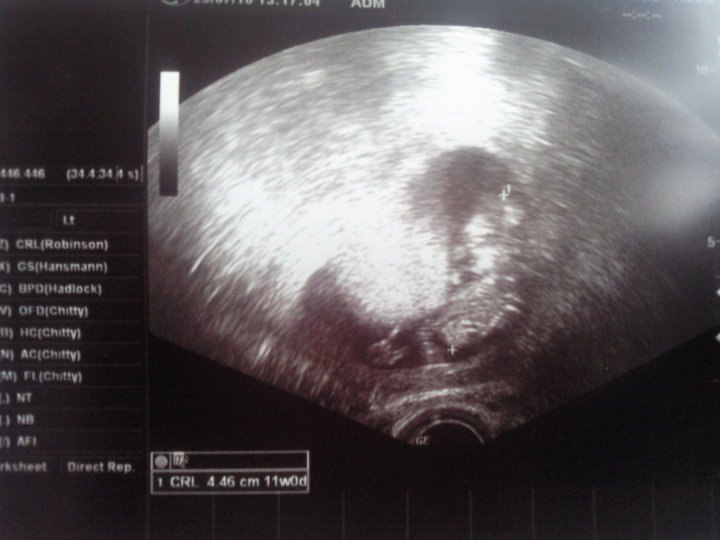

Billed 1: Vaginal termins scanning pga. ureglmæssig mens. 11+2